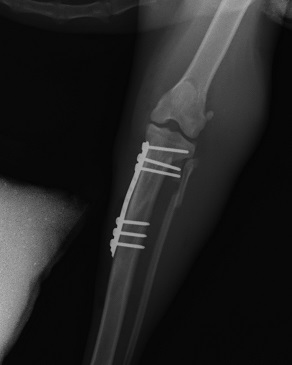

AO/ASIF internal fixation system is a cost effective method of fracture repair that has stood the test of time, and is adaptable to many fractures. We offer sizes from 1.5mm to 4.5mm and on occasion use a range of plates from veterinary cuttable plates to Limited Contact Dynamic Compression plates and hybrid plates.

We also offer Minimally Invasive Plate Osteosynthesis (MIPO) solutions to certain qualifying fractures and combination solutions for non-load sharing fractures.